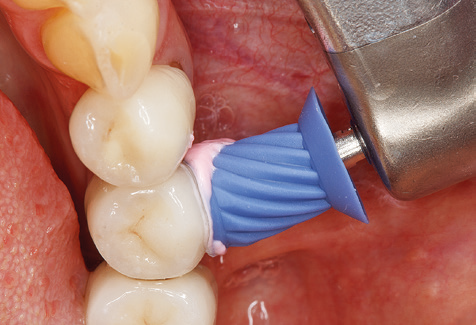

Good illumination of the working field facilitates the process considerably. The system used by the authors achieves this thanks to a 5x LED ring integrated in the handpiece. Naturally, a range of working tips for different indications is also offered. A straight, universally employable tip is the basic instrument required for machine cleaning of natural teeth (Fig. 5a and b). Curved tips, which allow access to exposed furcations, are also available for hard-to-reach areas in the posterior region (Fig. 6).

Fig. 4: Flexible probes with millimetre markings are recommended for the probing of dental implants (e.g. Colorvue Kit PCV11KIT6, Hu­Friedy). – Fig. 5a and b: A straight working tip (1P, W&H Dentalwerk Bürmoos GmbH) is a suitable instrument for use on all natural teeth. – Fig. 6: Curved working tips (3Pr/3Pl, W&H Dentalwerk Bürmoos GmbH) lend themselves to the processing of difficult-to-reach areas of the tooth and root surfaces (e.g. furcations). – Fig. 7: The tapered, hexagonal implant cleaning tip (1I, W&H Dentalwerk Bürmoos GmbH) permits atraumatic and efficient cleaning of the crown and abutment surfaces. – Fig. 8: Titanium and carbon curettes are suitable instruments for the manual cleaning of the implant surfaces.